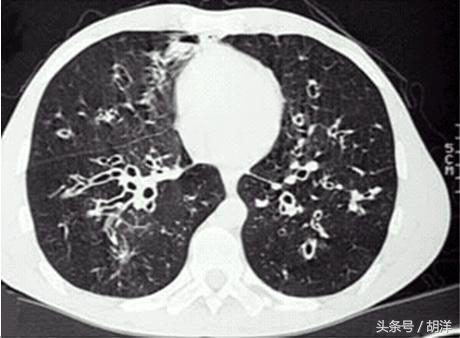

支气管扩张并不仅仅是支气管变得比正常粗了,正常支气管是有舒张和收缩功能的,具有弹性,有利于控制流入肺内的空气流速。有一些原因比如局部支气管反复的感染导致支气管管壁遭到破坏,负责收缩支气管管壁的平滑肌以及骨环均遭到破坏导致管壁收到周围组织的牵拉而局限性的变粗,这就好比山体中的通道半路长出了一个溶洞。正常的支气管管壁上都有负责搬运痰液的纤毛,而“溶洞”的墙壁上是没有搬运工的,大量的分泌物积存在溶洞中,细菌很容易在里面生长导致发热咳嗽咳痰,因此支气管扩张最重要的是管壁上搬运工的确实以及管壁组织的破坏。

在中国,导致支气管扩张的最重要原因是肺结核,由于中国是结核大国,结核患者众多,很多人即使肺结核治愈后也会在肺部留下后遗症,支气管扩张就是其中之一,因此中国支气管扩张患者数量众多,其他引起支气管扩张的原因还有肺炎、肺纤维化、弥漫性泛细支气管炎等疾病。